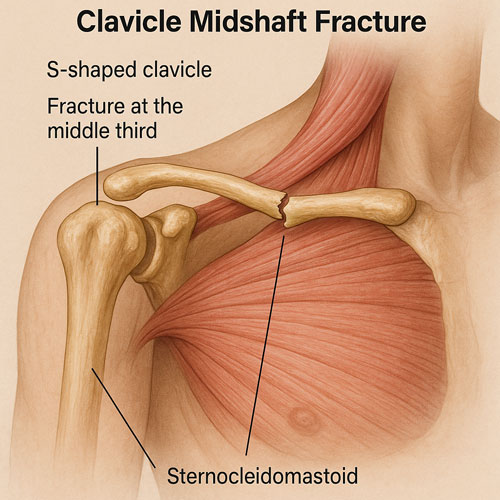

شکستگی وسط ترقوه

حدود ۸۰٪ شکستگیها در بخش میانی ترقوه (midshaft) اتفاق میافتد، زیرا این قسمت نازکتر و نیروهای مکانیکی بیشتری را تحمل میکند.